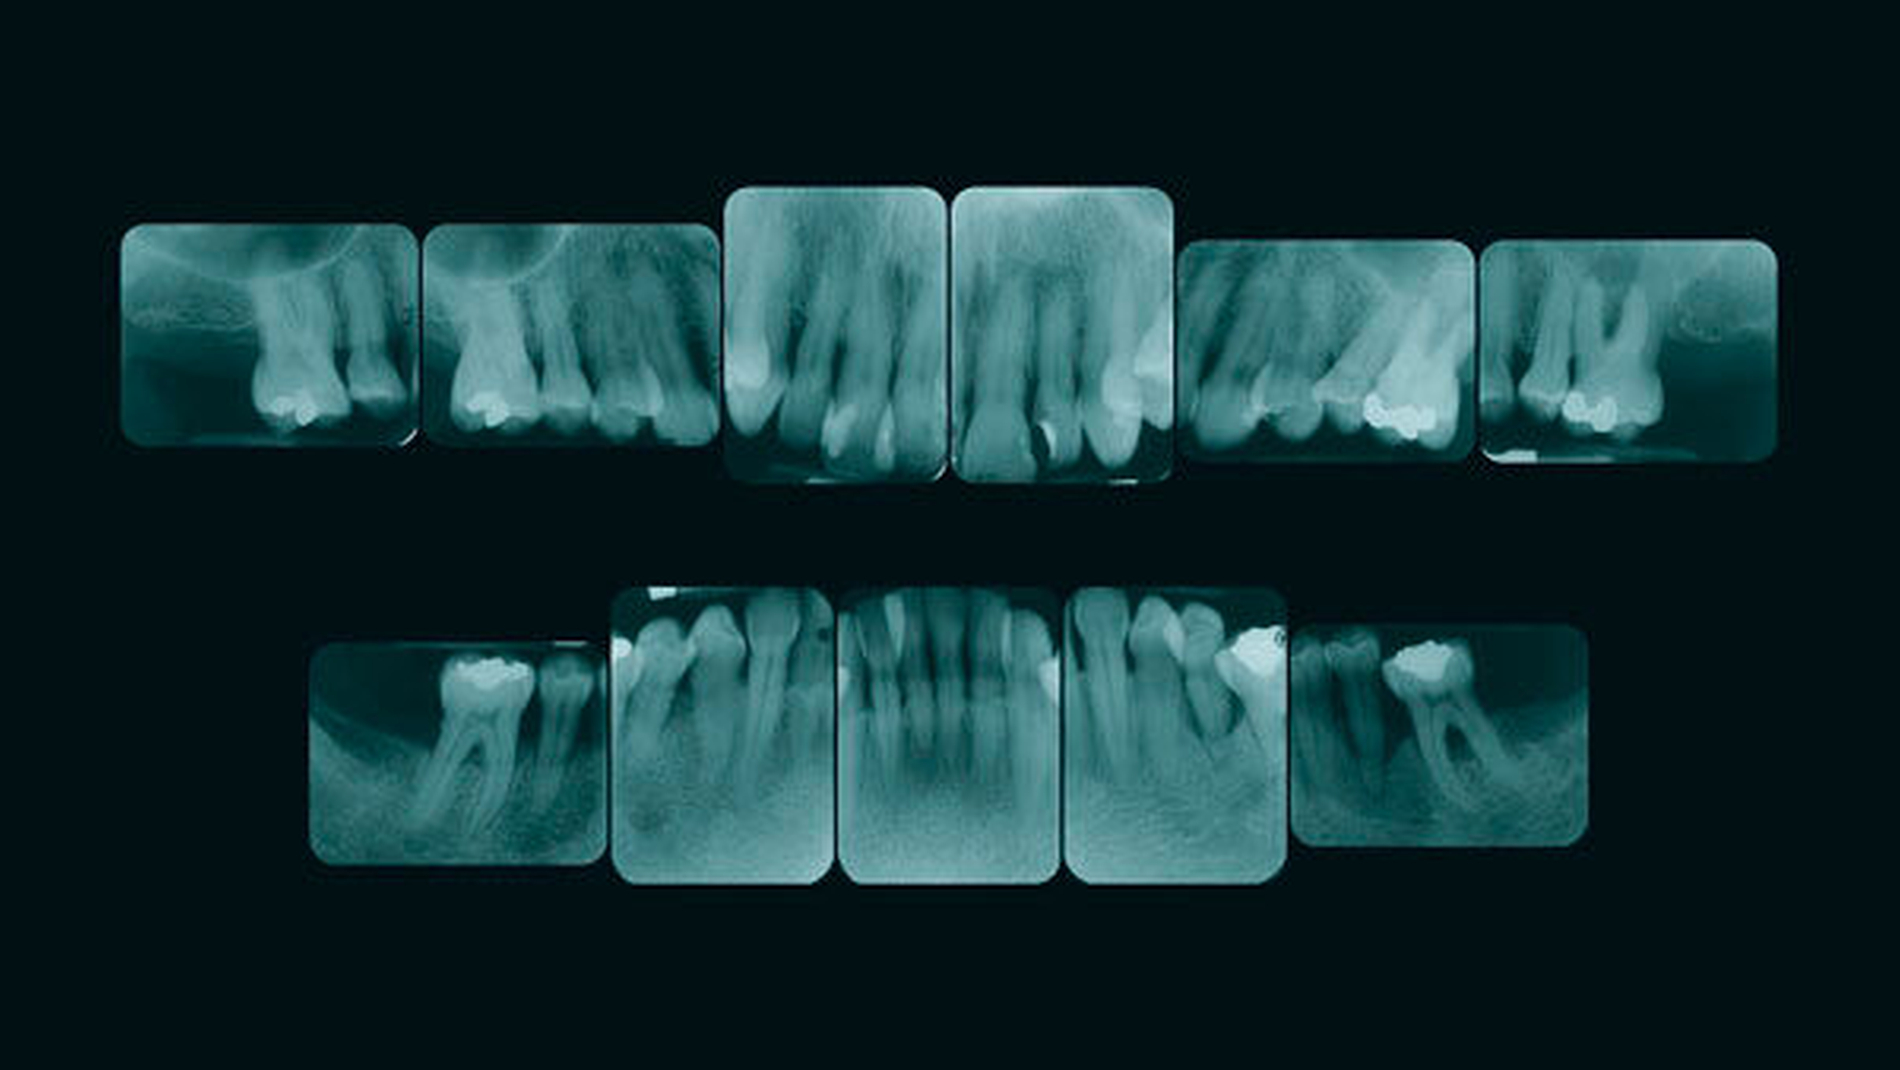

Röntgenbefund

Auf dem Röntgenstatus zeigt sich an den Zähnen 16, 13, 12, 11, 26, 35, 31, 41, 45 und 46 ein horizontaler Knochenabbau bis in das mittlere Wurzeldrittel oder darüber hinaus. Zahn 35 zeigt zusätzlich vertikalen Knochenabbau mesial und distal. Eine interradikuläre Aufhellung ist an den Zähnen 26, 36 und 46 zu sehen. Am Zahn 26 liegt eine periapikale Aufhellung vor. An Zahn 46 findet sich eine röntgendichte Ablagerung auf der Wurzelfläche im Sinne eines Konkrements. Der Zahn 11 ist elongiert.